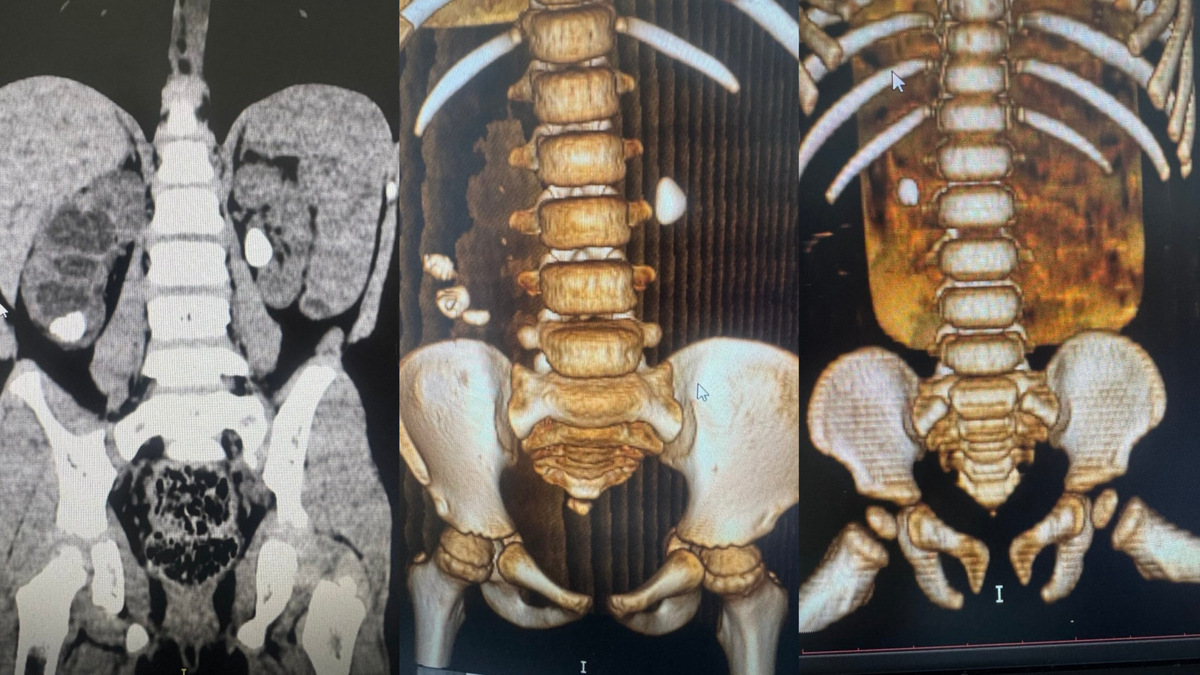

За 2025 год врачи детской городской клинической больницы №1 в городе Новосибирске обнаружили камни в почках у 118 детей. В 2024 году с подобным диагнозом лечились 82 ребёнка. Об этом сообщает пресс-служба Минздрава Новосибирской области.

В среднем размер камней у детей составляет 5-7 миллиметров. Рекордным стал показатель — 6 сантиметров. Самым юным пациентом с диагнозом мочекаменная болезнь в 2025 году был малыш в возрасте 11 месяцев.